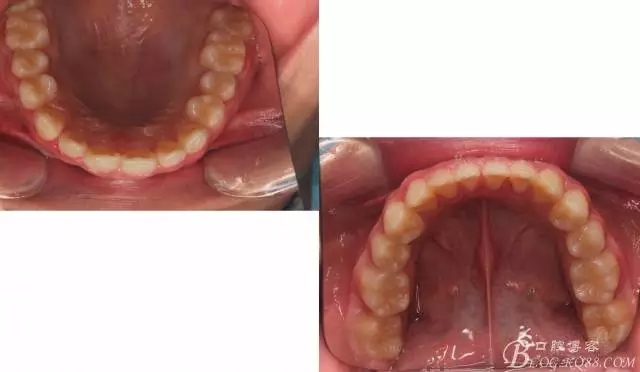

看看口內(nèi)照吧!真象“大暴牙”v假象“大暴牙”

三度深覆合,三度深覆蓋,尖牙,磨牙均二類關系!